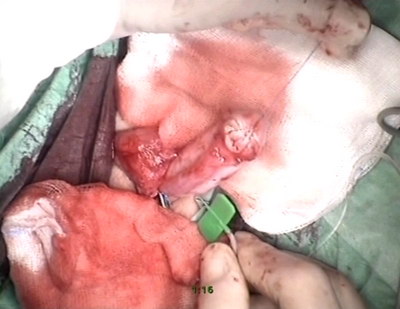

поверхности из наружного листка крайней плоти выкроен лоскут

размерами 8мм х 17 мм, по методике Hodgson перемещён на

валярную поверхность. По методике onlay произведена пластика

дистального отдела уретры непрерывным прецезионным швом